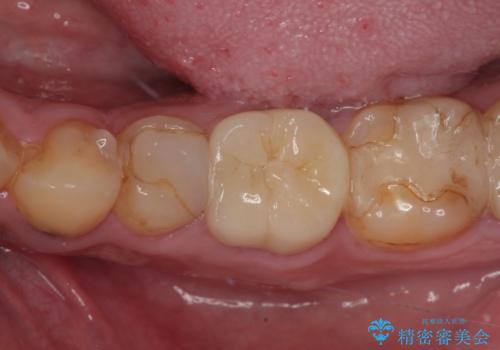

- 奥歯の歯肉から定期的に膿が出てくるとのことで来院された患者様です。

レントゲン写真などの診察を行った結果、根管治療が必要であったため、現在のクラウンを除去し、根管治療を行うこととしました。

根管治療後は症状を確認し、速やかにオールセラミッククラウンにて補綴治療を行うこととしました。